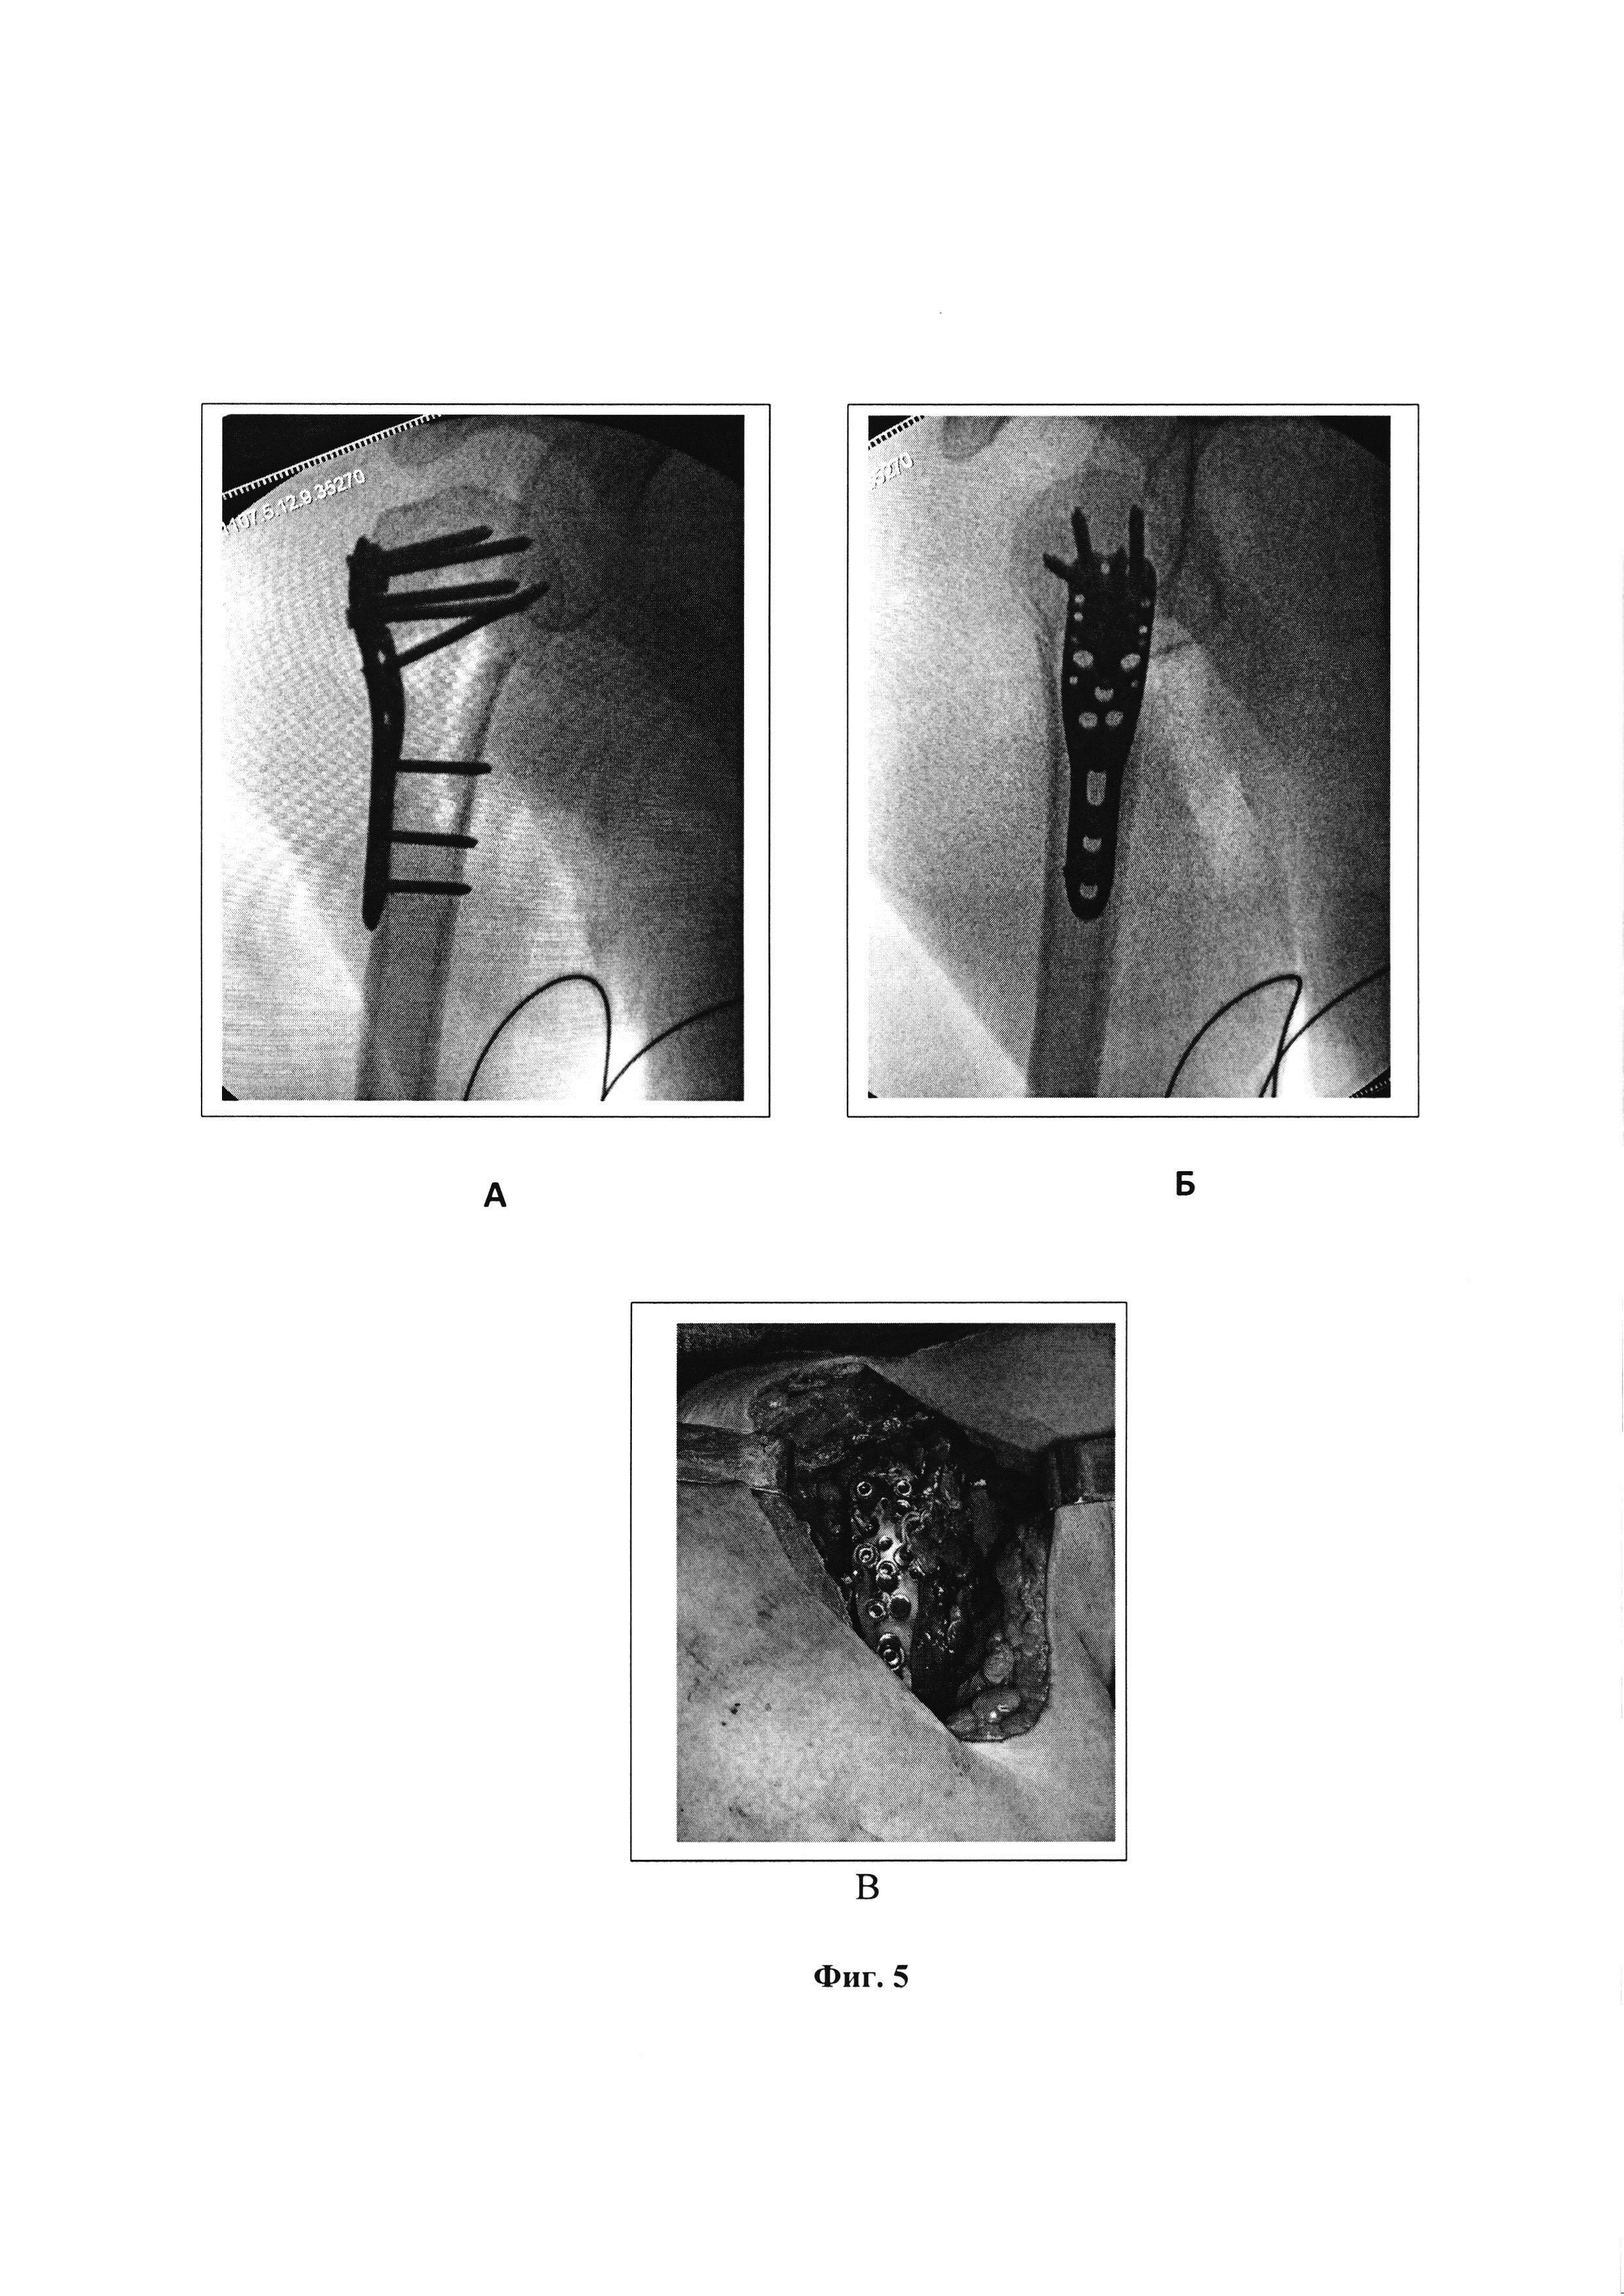

Область техники, к которой относится изобретение Изобретение относится к области медицины, а именно к травматологии, и может быть использовано для репозиции отломков при переломах проксимального отдела плечевой кости. Уровень техники Переломы проксимального отдела плечевой кости составляют около 5-7% от всех переломов у взрослых пациентов и занимают третье место по частоте среди переломов у пожилых пациентов после переломов проксимального отдела бедренной кости и дистального отдела лучевой кости. Переломы проксимального отдела плечевой кости составляют до 75% всех переломов плечевой кости у пациентов старше 60 лет, при этом у женщин они встречаются в 2-3 раза чаще, чем у мужчин [Ломтатидзе Е.Ш., Ломтатидзе В.Е., Поцелуйко С.В. [и др.] Анализ функциональных результатов внутреннего остеосинтеза при переломах проксимального отдела плечевой кости // Вестник травматологии и ортопедии им. Н.Н. Приорова. - 2003. - №3. - С. 62-66.]. Переломы данной локализации оказывают сильное влияние на функцию конечности в ближайшем и отдаленном периодах после травмы. Эпидемиологические исследования говорят о постоянном увеличении числа таких переломов и об удвоении их количества у пациентов в возрасте старше 80 лет в ближайшие 20 лет [Palvanen М., Kannus P., Niemi S., Parkkari J. Update in the epidemiology of proximal humeral fractures. Clin Orthop Relat Res 2006;442:87-92.; Song J.Q., Deng X.F., Wang Y.M., Wang X.B., Li X., Yu B. Operative vs. nonoperative treatment for comminuted proximal humeral fractures in elderly patients: a current metaanalysis. Acta Orthop Traumatol Turc. 2015;49(4):345-53.]. В настоящее время нет однозначных рекомендаций по выбору тактики лечения больных с переломами проксимального отдела плечевой кости. Это связано с большим количеством возможных вариантов лечения: консервативных и оперативных, большого количества модификаций оперативного метода лечения. Важную роль играет время, прошедшее с момента травмы до момента оперативного лечения. Задержка в проведении оперативного лечения более чем на 5 дней приводит к значительному увеличению количества осложнений таких, как аваскулярный некроз головки и вторичное смещение отломков. В случаях с раскалыванием головки плечевой кости и переломов в сочетании с вывихом анатомическая репозиция должна быть выполнена не позднее 48 часов после травмы, это снижает риск аваскулярного некроза головки плечевой кости [ При 3-х и 4-хфрагментарных переломах проксимального отдела плечевой кости неточная репозиция отломков плечевой кости (в частности большого бугорка), высокое стояние пластины и неплотное ее прилегание к кости, а также несостоятельность фиксации в послеоперационном периоде, приводит к развитию субакромиального импинджмента и плохим функциональным результатам лечения. Достижение одновременно правильного положения отломков, правильного позиционирования пластины и плотного ее прилегания к кости является сложной хирургической задачей. В настоящее время существует много способов фиксации отломков при переломах проксимального отдела плечевой кости, однако нет определенного алгоритма действий, который позволил бы добиться четкой анатомической репозиции при любом типе перелома, включая 3-х и 4-хфрагментарные переломы. Наиболее часто для репозиции отломков головки плечевой кости используют спицы в качестве джойстиков для репозиции отломков [Bucholz, Robert W.; Heckman, James D.; Court-Brown, Charles M.; Tornetta, Paul. «Rockwood And Green's Fractures In Adults, 7th Edition». Lippincott Williams & Wilkins. 2010. 1072-1075.]. Недостатком данного метода является сложность позиционирования спиц по причине смещения отломков головки плечевой кости под акромиальный отросток лопатки. Акромиальный отросток лопатки часто ограничивает амплитуду движения спиц-джойстиков, это приводит к необходимости проводить спицы несколько раз, что в свою очередь наносит дополнительную травму кости и окружающим мягким тканям. Кроме того, при проведении интенсивных манипуляций с отломками головки плечевой кости посредством спиц-джойстиков часто происходит их вырывание. Это особенно часто проявляется у пожилых пациентов со сниженной плотностью кости. Каждое вырывание спицы приводит к потере репозиции и требует повторного заведения джойстика. Потеря фиксации спицы-джойстика в кости (при ее вырывании) приводит к формированию костной полости в месте ее установки. Кроме того, частое перепроведение спиц-джойстиков приводит к дополнительной травме кости и окружающих мягких тканей, увеличению количества полостей в кости, уменьшению суммарной костной плотности головки плечевой кости (что особенно ощутимо при проведении остеосинтеза в условиях остеопороза или остеопении). Создание дополнительных костных полостей после спиц-джойстиков приводит к сложности окончательной фиксации перелома с помощью пластин, так как уменьшает фиксационные возможности винтов. Прошивание сухожилий мышц вращающей манжеты плеча (ВМП) рекомендуется многими авторами, как для репозиции, так и для усиления фиксации перелома. Однако рекомендации по тактике последовательности действий разнятся. Так Архипов С.В. и Ковалерский Г.М. прошивание сухожилий мышц вращающей манжеты плеча используют для репозиции отломка большого или малого бугорков, после чего осуществляют временную фиксацию отломков головки плечевой кости спицами Киршнера (2-3 спицы), одновременно с этим производят спицевую фиксацию проксимального отдела плеча к диафизу. После достижения временной фиксации позиционируют пластину, производят окончательную фиксацию перелома пластиной и удаляют провизорные спицы [Архипов С.В., Ковалерский Г.М. Хирургия плечевого сустава. Москва 2015 г. 171-173.]. Авторами также предлагается проведение компрессирующих винтов для достижения плотного контакта пластины с костью, а отверстия в пластине авторы используют для установки проволочных петель с целью дополнительной фиксации мелких отломков. Недостатком данного способа является предварительная фиксация отломков спицами (2-3 иногда и более). Проведение провизорных фиксирующих спиц в дальнейшем создает помехи для уложения и позиционирования пластины. Проведенные провизорные спицы часто проходят через зону максимальной костной массы отломка. Пластину приходится укладывать в обход спиц, это приводит к тому, что блокируемые винты, проходящие через пластину и фиксирующие отломки, идут через зону меньшей косной массы отломка. Перепроведение же спиц приводит к потере временной репозиции и к смещению отломков. Подшивание к пластине сухожилий только подостной и надостной мышц, без обязательного прошивания подлопаточной мышцы создают дисбаланс в плотности прилегания пластины к кости. Из уровня техники для фиксации переломов проксимального отдела плечевой кости известно использование пластин с прошиванием сухожилий мышц ВМП для репозиции отломков бугорков. При этом вначале проводят прошивание сухожилий, потом нити продевают через пластину, производят репозицию и фиксацию пластины к кости [Nho S.J., Brophy R.H., Barker J.U., Cornell C.N., & Macgillivray J.D. Innovations in the management of displaced proximal humerus fractures. The Journal of the American Academy of Orthopaedic Surgeons, 15 1 (2007), 12-26.]. Однако, прошивание сухожилий ВМП нитями только при наличии перелома в точке фиксации создает дисбаланс сил при натяжении этих нитей (то есть при репозиции отломков), что усложняет процесс позиционирования пластины. К этому же приводит и отсутствие центральной спицы, которая центрирует пластину и тем самым осуществляет плотное прижатие (правильно позиционированной) пластины к кости. Основная проблема, с которой встречается хирург при репозиции отломков и позиционировании пластины, это сложность достижения правильной и минимально травматичной репозиции отломков без помех для укладки пластины. Из уровня техники известно использование прошивания сухожилий мышц ВМП и их подшивание к пластине для увеличения прочности фиксации. Однако прошиваются только сухожилия, крепящиеся к сломанным фрагментам (сухожилия надостной и подостной мышц при переломах большого бугорка, сухожилие подлопаточной мышцы при переломах малого бугорка). Для репозиции же авторы используют большое количество спиц Киршнера и зажимы (в частности зажим Лоумена) [Lynn A. Crosby, Robert J.Neviaser Proximal humerus fractures. Evaluation and management. Springer. 2015. 99-105.]. Применение большого количества спиц Киршнера, как уже было сказано, усложняет позиционирование пластины и проведение через нее винтов. Использование для репозиции зажимов наносит дополнительную травму окружающим мягким тканям, и имеет риск повреждения огибающих плечевую кость артерий (в частности задней огибающей) и подмышечного нерва. Наиболее близким к заявляемому решению является способ остеосинтеза при переломе проксимального отдела плечевой кости (Патент на изобретение №2673146), в котором для репозиции отломков плечевой кости используют прошивание сухожилий мышц ВМП, для фиксации - штифт. Способ согласно изобретению осуществляют следующим образом. Выполняют разрез кожи и подкожной жировой клетчатки длиной 5-6 см между передним и средним пучками дельтовидной мышцы от переднелатерального угла акромиона до проекции подмышечного нерва. Разводят дельтовидную мышцу. Прошивают отдельными нитями сухожилия надостной, подостной и подлопаточной мышц, по меньшей мере, двумя стежками каждое, причем сухожилия надостной и подостной мышц прошивают на расстоянии 1-1,5 см от мест их прикрепления к большому бугорку плечевой кости, а сухожилие подлопаточной мышцы - на расстоянии 1-1,5 см от места его прикрепления к малому бугорку плечевой кости. Репозицию отломков проводят путем тракций за концы проведенных через сухожилия нитей, при этом сначала проводят репозицию большого бугорка путем тракций в латеральном и дистальном направлениях за концы нитей, проведенных через сухожилия надостной и подостной мышц, затем ротируют головку плечевой кости путем тракций в дорсальном направлении за концы нити, проведенной через сухожилие подлопаточной мышцы. Сохраняя тягу за нити, выполняют продольный разрез длиной 1-1,5 см сухожилия надостной мышцы, через который формируют в головке плечевой кости входное отверстие для штифта. После введения штифта его фиксируют с помощью блокирующих винтов, проводимых через отверстия штифта, причем проксимальные блокирующие винты проводят через большой и малый бугорки плечевой кости, а дистальный блокирующий винт - через диафиз плечевой кости. К шляпкам винтов фиксируют с натяжением проведенные через сухожилия нити, при этом к винтам, расположенным в области большого бугорка плечевой кости, фиксируют нити, проведенные через сухожилия надостной и подостной мышц, а к винту, проведенному через малый бугорок плечевой кости, фиксируют нити, проведенные через сухожилие подлопаточной мышцы. Способ позволяет уменьшить травматичность и длительность вмешательства, повысить надежность репозиции, предотвратить нарушение кровоснабжения головки плечевой кости. Однако для того чтобы прошить все перечисленные сухожилия, хирургу необходимо произвести достаточно широкий хирургический доступ. Хирургический доступ через дельтовидную мышцу ограничен снизу анатомическим ходом подмышечного нерва. Существующий трансдельтовидный доступ должен проходить не далее 5 см ниже акромиона, иначе существует риск повреждений ствола подмышечного нерва. Расположение подмышечного нерва ориентировочное и существуют анатомические особенности, которые могут приводить к более высокому расположению нерва. Чем шире хирургический доступ, тем выше риск повреждения подмышечного нерва. При этом в передних отделах подмышечный нерв представлен уже не в виде четкого ствола, а в виде множества ветвей, которые иннервируют переднюю порцию дельтовидной мышцы. Производя широкое разведение дельтовидной мышцы (на 5-6 см от акромиона) хирурги пересекают все мелкие, идущие к передней части дельтовидной мышцы, пучки нервов. Это приводит к денервации и атрофии передней порции дельтовидной мышцы. Чем меньше разводятся пучки дельтовидной мышцы, тем больше мелких ветвей подмышечного нерва будет сохранено. Кроме того, предложенная последовательность прошивания сухожилий надостной, подостной и подлопаточной мышц, по меньшей мере, отдельными нитями с двумя стежками каждое, является менее удобной, зачастую приводящая к применению дополнительных устройств для доступа к сухожилию надостной мышцы, т.к. после переломов, смещение отломков таково, что сухожилие надостной мышцы уходит часто глубоко под акромион и физически вытащить его от туда для прошивания без специальных приспособлений (спиц, элеваторов и т.д.) не возможно. Кроме того, способ репозиции фрагментов кости в известном решении сопряжен с высоким риском их смещения при введении импланта, в связи с тем, что после прекращения тракций за нити отломки возвращаются на место под действием силы мышц, и при введении штифта нет центра приложения сил во время тракций. При этом установка проксимальных блокирующих винтов подразумевает наличие громоздких направителей, которые мешают сохранению тракций за джойстики. Кроме того, фиксация нитей «джойстика» к шляпкам винтов также имеет свои недостатки. Шляпки винтов для блокирующего штифта имеют бочкообразный вид. При введении винтов плотно к кости, места для накидывания на головку винта нити совсем не остается. Это может приводить к соскакиванию нити со шляпки винта и ослаблению фиксации. Недовведение винта до кости для облегчения фиксации нити вокруг него может приводить к субакромиальному импинджменту (соударению шляпки винта и акромиального отростка лопатки). Помимо этого, прикрепление нитей от надостной и подостной мышц к винту фиксирующему большой бугорок (точку прикрепления этих мышц), а от сухожилия подлопаточной мышцы к винту, проведенному через малый бугорок, увеличивает вырывающую силу, приложенную к винту. Кроме того, данный вид остеосинтеза можно применять только в ранние сроки после травмы. Через 5-7 дней формирующиеся между отломками рубцы не позволят произвести точную репозицию отломков по данной методике, или потребуют дополнительных хирургических доступов. Так же дополнительную травму суставу наносит разрез надостной мышцы (1-1,5 см) для формирования канала для введения штифта. Решаемой технической проблемой является разработка технически несложного, анатомичного и малотравматичного способа остеосинтеза переломов проксимального отдела плеча, включая 3-х и 4-х фрагментарные переломы, переломы в условиях снижения костной плотности, путем остеосинтеза их пластиной, обеспечивающего адекватную репозицию отломков, их надежную фиксацию и профилактику вторичного смещения в любые сроки после травмы. Раскрытие сущности изобретения Техническим результатом, на достижение которого направлено заявленное изобретение, является обеспечение надежной фиксации отломков как при простых 2-х фрагментарных, так и при тяжелых 3-4 фрагментарых переломах проксимального отдела плечевой кости, на любых сроках после травмы, при минимизации риска развития осложнений, обусловленных оперативным вмешательством. Технический результат достигается за счет реализации способа остеосинтеза при переломе проксимального отдела плечевой кости, включающий хирургический доступ к плечевому суставу, прошивание отдельными нитями сухожилий надостной, подостной и подлопаточной мышц с последующей репозицией отломков посредством тракций за концы проведенных через сухожилия нитей, после чего проводят остеосинтез с использованием импланта с фиксацией концов нитей к импланту и фиксацией импланта к плечевой кости блокирующими винтами, при этом: - к плечевому суставу осуществляют дельтопекторальный доступ с разрезом кожи и подкожной жировой клетчатки между дельтовидной и большой грудной мышцами; - в качестве импланта используют пластину с отверстиями для проведения блокирующих винтов для остеосинтеза проксимального отдела плечевой кости; - прошивание сухожилий проводят сначала подлопаточной мышцы, затем надостной и подостной; - после прошивания сухожилий концы нитей продевают через предназначенные для проведения нитей отверстия в пластине, центрируют пластину относительно суставной поверхности плечевой кости, после чего в центральное отверстие в пластине устанавливают центральную спицу, с последующей репозицией отломков путем тракций за концы нитей, удерживая пластину с проведенной центральной спицей; - концы нитей фиксируют к отверстиям в пластине. Прошивание сухожилий подлопаточной, надостной и подостной мышц проводят нерассасывающимися нитями (Терилен 5, FiberWire 2 и др.) на расстоянии 1 см от места прикрепления сухожилия к точке фиксации (большому или малому бугорку), как показано на фиг. 1, 2. При этом каждое сухожилие прошивают нитью крестообразным швом с двукратным пересечением под прямым углом лини шва, расположенной параллельно соответствующей торцевой стороне пластины, с выводом концов нитей с внешней стороны сухожилия. Прошивание осуществляют в последовательности 1-6, указанной на фиг. 1. В способе используют предизогнутую пластину для проксимального отдела плечевой кости. Оперативный доступ производят через стандартный дельто-пекторальный доступ. Выполняют разрез кожи и подкожно-жировой клетчатки начиная от клювовидного отростка лопатки до в/3 плеча длинной 15 см., находят v.cephalica, и отводя ее латерально осуществляют доступ между дельтовидной и большой грудной мышцами к плечевому суставу. Для проведения репозиции концы нитей идущих от сухожилий продевают через отверстия в пластине, соответствующие направлению хода волокон сухожилия: нити, идущие от подлопаточной мышцы продевают через отверстия на переднем краю пластины, нити от надостной мышцы - через задне-верхние отверстия в пластине, нити от подостной мышцы - через отверстия, расположенные по заднему краю пластины. Центрируют пластину после продевание нитей через отверстия в пластине под электронно-оптическим преобразователем, ориентируясь на суставную поверхность плечевой кости так, чтобы угол между плоскостью суставной поверхности и продольной осью пластины соответствовал шеечно-диафизарному углу плечевой кости, после чего устанавливают центральную спицу, проходящую через центр пластины и центр головки плечевой кости, при этом добиваются правильного угла наклона суставной поверхности головки плечевой кости к продольной оси пластины (оптимально 130°). Репозицию отломков путем тракций за концы нитей осуществляют посредством натяжения нитей (всех 3 нитей одновременно), фиксирующих ВМП, прижимая пальцем пластину к проксимальному отделу плечевой кости. При этом сначала производится натяжение нитей и только потом, при натянутых нитях, осуществляют прижатие пластины к уже репонированным отломкам плечевой кости. Эта манипуляция позволяет добиться быстрой и качественной репозиции отломков и обеспечить плотное прилегание пластины к кости. Пластину фиксируют к проксимальному отделу плечевой кости блокируемыми винтами. Удерживают нити и плотно прижимают пластину к кости, производят рассверливание по направителю наиболее удобных для вкручивания винтов отверстий. После чего фиксируют пластину винтами. Первыми используют отверстия, находящиеся в верхне-переднем квадрате пластины, так как они просты в установке из имеющегося хирургического доступа и позволяют зафиксировать пластину изолированно к проксимальному отделу кости. Проведя проксимальные винты, фиксируют пластину к диафизу кости через овальное отверстие кортикальным винтом 3,5 мм, позиционируя передний край пластины позади сухожилия длинной головки двухглавой мышцы. Контролируют положение отломков на ЭОП. Фиксацию концов нитей к отверстиям в пластине осуществляют путем поочередного завязывание нитей. Первым фиксируют к пластине сухожилие подлопаточной мышцы. В положении внутренней ротации плеча нити завязываются на 6 узлов. Далее в положении отведения и наружной ротации плеча фиксируют так же 6-ю узлами сухожилие надостной мышцы. Последним этапом, в положении наружной ротации плеча фиксируют к пластине сухожилие подостной мышцы. Так как длина кортикального винта которым изначально фиксируется диафиз кости часто велика, то он в дальнейшем его заменяют на более короткие блокирующие винты. Кроме того, данный способ остеосинтеза осуществим на любых сроках после травмы, не требует дополнительного разреза сухожилия надостной мышцы, и производится через анатомически безопасный интервал между мышцами (дельтовидной и большой грудной), исключающий повреждение дельтовидной мышцы (как основной силы осуществляющей движения в плечевом суставе). Таким образом, в заявляемом решении в отличие от способа - прототипа, выполняют дельтопекторальный доступ, который осуществляется между дельтовидной и большой грудной мышцами, который позволяет осуществить широкий хирургический доступ к плечевому суставу, без риска послеоперационных неврологических осложнений. Прошивание первым этапом сухожилия подлопаточной мышцы и тракция за данный джойстик позволяет «вытащить» сухожилие надостной мышцы из-под акромиона и значительно более проще прошить сухожилия, не используя металлические инструменты. Репозиция отломков осуществляется одновременно с их фиксацией к пластине, тем самым нет риска их смещения при введении импланта. Наличие центральной спицы создает вектор приложения всех сил, который направлен к пластине. За счет одновременной тракций за джойстики и прижимания пластины к кости создается репозиционный момент, который способствует одновременной репозиции всех сухожилий и отломков. Фиксация отломков в пластине происходит без громоздких направителей, что облегчает сохранение натяжение нитей и сохранение репозиции отломков. Фиксация нити в отверстии в пластине (по сравнению с прототипом, где фиксация осуществляется к шляпкам винтов) является значительно более надежной, при этом отсутствует риск ослабления фиксации. Поочередное прошивание всех сухожилий мышц ВМП независимо от наличия перелома костного фрагмента в точке прикрепления позволяет реализовать репозицию отломков с помощью нерассасывающихся нитевых джойстиков. Репозиция достигается с помощью установки центральной спицы и баланса между нитевыми джойстиками. Центральная спица, а также обязательное прошивание всех трех сухожилий мышц ВМП позволяет правильно распределить силы при репозиции, при этом не смещая пластину (из-за дисбаланса нитей). Дисбаланс нитей, может развиваться, во-первых, при их наложении не за все три сухожилия. Во-вторых, даже при наложении нитей за все три сухожилия, при отсутствии центральной спицы, тракция за нити приводит к смещению пластины кверху и кзади. Попытки одновременно удержать пластину в правильном положении и соблюсти баланс между нитями приводят или к недонатяжению нитей (и возможно к недорепозиции отломков) или к нарушению положения пластины (больше кверху и кзади, что может приводить к субакромиальному импинджмент синдрому). Подтягивание сухожилия мышц ВМП к пластине (при натягивании нитевых джойстиков) позволяет поставить костный отломок большого бугорка под пластину, тем самым обеспечивая его плотное прижатие последней после выполнения окончательного остеосинтеза и в тоже время фиксацию его винтом через зону максимальной костной массы отломка. Разработанная оригинальная последовательность манипуляций позволяет добиться быстрой, точной и надежной репозиции, а также стабильной фиксации при любых типах переломов проксимального отдела плечевой кости (3-х, 4-х фрагментарных, в том числе и условиях остеопороза). При осуществлении способа обеспечивается плотная фиксация пластины к проксимальному отделу плечевой кости, что позволяет минимизировать риск осложнений, например, импинджмета пластиной, так как уменьшается зазор между пластиной и костью и пластина легко заходит в субакромиальное пространство при отведении плеча. Краткое описание чертежей Изобретение поясняется чертежами, где на фиг. 1 представлена схема прошивания подлопаточной мышцы, на фиг. 2 - схема проведения нитей через пластину, на фиг. 3 представлены этапы репозиции отломков проксимального отдела плечевой кости: А -поочередное прошивание сухожилий мышц ВМП, позиционирование пластины, установка центральной спицы, продевание нитей через соответствующие отверстия в пластине; Б, В - натяжение нитей, репозиция отломков; Г, Д - интраоперационные рентгенограммы до и после репозиции: на фиг. 4 - этапы репозиции отломков проксимального отдела плечевой кости: произведена фиксация пластины к проксимальному отделу плечевой кости блокируемыми винтами и фиксация диафиза кортикальным винтом 3,5 мм; на фиг. 5 - конечный этап операции: А, Б - рентгенологический контроль положения отломков и фиксатора; В - вид раны, фиксация нитей к пластине; на фиг. 6 - рентгенограммы, демонстрирующие клинический пример: А и Б - рентгенограммы после травмы; В - после операции; Г и Д - через 3 месяца после операции; Е и Ж - через 6 месяцев после операции, перелом сросся. Осуществление изобретения Последовательность действий по остеосинтезу при переломах проксимального отдела плечевой кости заключается в следующем. Вначале прошивают сухожилия мышц ВМП, затем нити продевают через пластину, далее устанавливают центральную спицу позволяющую центрировать натяжение нитей-джойстиков, и репонировать отломки плечевой кости. Последовательность прошивания сухожилий: вначале прошивают сухожилие подлопаточной мышцы, затем сухожилие надостной мышцы, после чего - сухожилие подостной мышцы. Данная последовательность дает возможность поэтапно достичь репозиции отломков головки плечевой кости. Первый шов проводят через наиболее доступное при переднем дельто-пекторальном доступе сухожилие подлопаточной мышцы. В дальнейшем манипуляция с первым джойстиком-держалкой позволяет достичь частичной репозиции головки плечевой кости и облегчить доступ к сухожилию надостной мышцы, которое находится глубоко в субакромиальном пространстве. Прошивание вторым этапом сухожилия надостной мышцы и манипуляция данным (вторым) джойстиком позволяет получить доступ и прошить еще более тяжело достигаемое (через передний дельтопекторальный хирургический доступ) сухожилие наружного ротатора (подостной мышцы). При использовании пластин для проксимального отдела плечевой кости их отверстия применяются для подшивания к пластине сухожилий мышц вращающей манжеты плеча. Однако данная манипуляция (по рекомендациям производителя) применяется при переломах соответствующих участков плечевой кости (точек прикрепления данных сухожилий). В изобретении предлагается прошивать все три сухожилия мышц независимо от наличия перелома соответствующего фрагмента плечевой кости, т.к. это позволяет достичь правильного баланса сил при репозиции отломков и улучшить плотность прилегания пластины к кости, тем самым увеличивая прочность фиксации перелома. Ниже представлено более детальное описание заявляемого способа. Операцию производят под проводниковой анестезией в положении больного на спине. Укладку больного выполняют эксцентрично относительно продольной оси операционного стола, смещая поврежденное плечо ближе к центру стола. Голову пациента фиксируют дополнительными упорами, электронно-оптический преобразователь располагают со стороны здорового надплечья. Оперативный доступ производят через дельто-пекторальный доступ. Выполняют разрез кожи и подкожно-жировой клетчатки начиная от клювовидного отростка лопатки до в/3 плеча длинной 15 см., находят v.cephalica, и отводя ее латерально осуществляют доступ между дельтовидной и большой грудной мышцами к плечевому суставу. После доступа к плечевой кости, поочередно идентифицируют: большую грудную мышцу, выходящее из-под нее сухожилие длинной головки двухглавой мышцы, короткую головку двухглавой мышцы. Прослеживают сухожилие длинной головки двухглавой мышцы до уровня межбугорковой борозды и идентифицируем большой и малый бугорки плечевой кости. От малого бугорка начинается сухожилие подлопаточной мышцы, которое идет под короткой головкой двухглавой мышцы. Первым этапом находят сухожилие подлопаточной мышцы и прошивают. Прошивание сухожилия подлопаточной мышцы производят нерассасывающимися нитями (например, Терилен 5, FiberWire 2) на расстоянии 1 см от малого бугорка. Далее нити берут на держалку (фиг. 1). Вторым этапом производят прошивание сухожилия надостной мышцы. Для этого идентифицируют акромиально-клювовидную связку, отводят ее вверх, после чего осуществляя тракцию за сухожилие подлопаточой мышцы, находят и выводят для прошивания из под акромиального отростка лопатки сухожилие надостной мышцы. Схема прошивания сухожилия и тип нитей одинаковы для всех сухожилий мышц вращающей манжеты плеча. Причем, чем тоньше и прочнее используемые нити, тем меньшими будут узлы после фиксации сухожилий к пластине. Третьим этапом идентифицируют и прошивают сухожилие подостной мышцы. Сухожилие мышцы крепится к середине заднего края большого бугорка. Для облегчения прошивания сухожилия подостной мышцы используют тракцию за сухожилие надостной мышцы. В результате получают три нитевых джойстика (подлопаточный, надостный и подостный). Данные джойстики позволяют в полном объеме контролировать положение отломков и головки плечевой кости без риска их прорезывания, что часто происходит со спицевыми джойстиками в условиях сниженной костной массы у пожилых людей. Следующим этапом является поочередное продевание нитей, идущих от сухожилий ВМП (вращающей манжеты плеча), через соответствующие отверстия в пластине для проксимального отдела плечевой кости (фиг. 2). Особенностью остеосинтеза 4-х фрагментарных переломов проксимального отдела плечевой кости является проведение костной пластики до использования пластины. Могут быть использованы костные аллотрансплантаты для заполнения дефекта между бугорками и отломком суставной поверхности. Далее производят позиционирование пластины, располагая ее позади межбугорковой борозды и на 5 мм ниже верхнего края большого бугорка. После чего фиксируют пластину одной центральной спицей Киршнера. Установка центральной спицы является важным моментом операции. Данная спица является опорной. Ее наличие позволяет центрированно прижимать пластину при натяжении нитей, в тоже время установка данной центральной спицы определяет вектор репозиции сломанных участков проксимального отдела плечевой кости. Прошивание же сухожилий мышц ВМП, крепящихся к несломанным фрагментам, создает компенсаторные силы, препятствующие искривлению спицы и однобокому (ацентричному) смещению пластины, что также формирует правильный вектор репозиции сломанных фрагментов. Положение пластины проверяют на ЭОП (Электронно-оптическом преобразователе), ориентируясь по расположению центральной спицы. После чего производят натяжение нитей фиксирующих ВМП, прижимая пальцем пластину к проксимальному отделу плечевой кости. Эта манипуляция позволяет добиться быстрой и качественной репозиции отломков и обеспечить плотное прилегание пластины к кости (фиг. 3 А-Д). Следующим этапом является фиксация пластины к проксимальному отделу плечевой кости блокируемыми винтами. Пластину устанавливают накостно, что не требует проведения дополнительного разреза сухожилия надостной мышцы. Удерживая нити и плотно прижимая пластину к кости, производят рассверливание по направителю наиболее удобных для вкручивания винтов отверстий. После чего фиксируют пластину винтами. Первыми следует использовать отверстия, находящиеся в верхне-переднем квадрате пластины, так как они просты в установке из имеющегося хирургического доступа и позволяют зафиксировать пластину изолированно к проксимальному отделу кости. Проведя проксимальные винты, фиксируют пластину к диафизу кости через овальное отверстие кортикальным винтом 3,5 мм, позиционируя передний край пластины позади сухожилия длинной головки двухглавой мышцы. Контролируют положение отломков на ЭОП (фиг. 4). Вкручивание диафизарного винта позволяет добиться правильной репозиции диафиза относительно проксимального отдела кости. Следующим этапом производят затягивание и фиксацию нитей к пластине, удаление центральной спицы и установка дополнительных винтов. При этом подлопаточную мышцу фиксируют через отверстия на переднем краю пластины, надостную мышцу - через задне-верхние отверстия в пластине, подостную мышцу - через отверстия расположенные по заднему краю пластины. Так как длина кортикального винта, которым изначально фиксируется диафиз кости, часто велика, то он в дальнейшем заменяется на более короткие блокирующие винты (фиг. 5). Фиксация отломков пластиной осуществляется по принципам абсолютной стабильности, что позволяет добиться прочной фиксации и начать раннюю реабилитацию. В 2017-2018 годах в отделении неотложной травматологии опорно-двигательного аппарата НИИ скорой помощи им. Н.В. Склифосовского, согласно заявляемому способу было прооперировано 32 пациента (27 женщин и 5 мужчин) старше 60 лет с переломами шейки плечевой кости. Средний возраст пострадавших 71,4 года. Таблица 1. Распределение пациентов с переломами проксимального отдела плечевой кости по полу и типу перелома. Всем больным при поступлении производили рентгенологическое исследование в 2-х проекциях, оценивали индекс кортикального слоя (ИКС) по Tingard, который определяется как среднее арифметическое толщины 4-х кортикальных слоев на стандартных прямых рентгенограммах. Для исследования были отобраны пациенты с пониженной минеральной плотностью кости, у которых ИКС был менее 4 мм. У всех пациентов причиной перелома была низкоэнергетичная травма. Оперативное лечение производили в первые 4-5 дней после травмы. Фиксацию перелома проводили блокируемыми пластинами для проксимального отдела плеча (DC или PHILOS). После проведения остеосинтеза проводили рентгенологическое исследование для оценки качества репозиции (в том числе шеечно-диафизарного угла). В послеоперационном периоде руку фиксировали косыночной повязкой на 5 недель. С 1 дня после операции назначали активную лечебную гимнастику. Количество и интенсивность упражнений увеличивали по мере уменьшения болевого синдрома. Контрольные обследование больных проводили в сроки 1,5; 3 и 6 месяцев. Оценивали жалобы пациентов (в частности интенсивность болевого синдрома), объем движений в плечевом суставе, проводили рентгенологическое исследование в 2-х проекциях и ультразвуковое исследование плечевого сустава. У всех прооперированных пациентов интраоперационно удалось добиться удовлетворительной репозиции и правильного шеечно-диафизарного угла. Оценка результатов лечения. При оценке рентгенологических данных. • Достигнутое интраоперационно положение отломков и шеечно-диафизарный угол сохранялись в течение всего срока наблюдения. • У всех прооперированных пациентов переломы срослись. При оценке данных ультразвукового исследования выявили. Оценка функциональных результатов пациентов прооперированных по вышеуказанной методике. Клинический пример. Пациентка 76 лет. 4-х фрагментарный перелом. Пациентка прооперирована по предложенной методике. Интраоперационно удалось добиться правильного положения отломков. При динамическом наблюдении за пациенткой отмечено сохранение достигнутого положения отломков и отсутствие признаков несостоятельности фиксации. Перелом сросся. Данные УЗИ коррелировали с функцией плечевого сустава. Через 6 месяцев после операции отведение и сгибание были более 170 градусов.